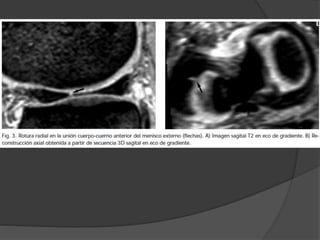

Reporte de roturameniscal  Localización:  tercios (cuerno anterior, cuerpo y cuerno posterior) ○ Raíces meniscales centrales, unión de tercios  Anchura del menisco se divide también en tercios(periférica, zona blanca y borde interno o libre)

Reporte de roturameniscal  Si es completa o no  Longitud aproximada  Rupturas múltiples se describen cada una por separado  Plano  Axial: ○ Vertical: paralelas (long) o perpendiculares(radiales) ○ Horizontal

 Forma:  Picode loro, rotura oblicua con una orientación radial en el borde libre meniscal con un trayecto paralelo al eje del menisco cuando se extiende perifericamente  Mixtas: forma de estrella  Asa de cubo: fragmento interno desplazado en la escotadura intercondílea ○ Los fragmentos menores de un tercio del menisco, pueden no ser detectados ○ Las roturas del menisco interno en asa tipicamente se localizan bajo el LCP= signo doble LCP ○ Diferenciar de :LCA roto, ligamento meniscofemoral roto, fragmento libre en la escotadura intercondílea